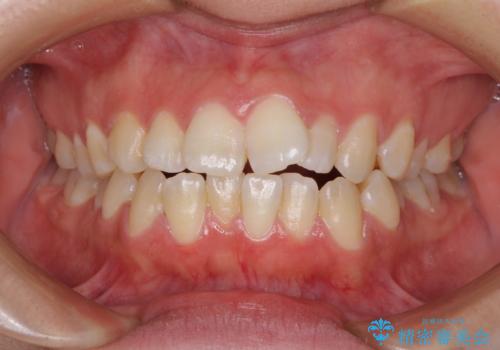

顕著な八重歯をインビザラインで治せるところまで改善